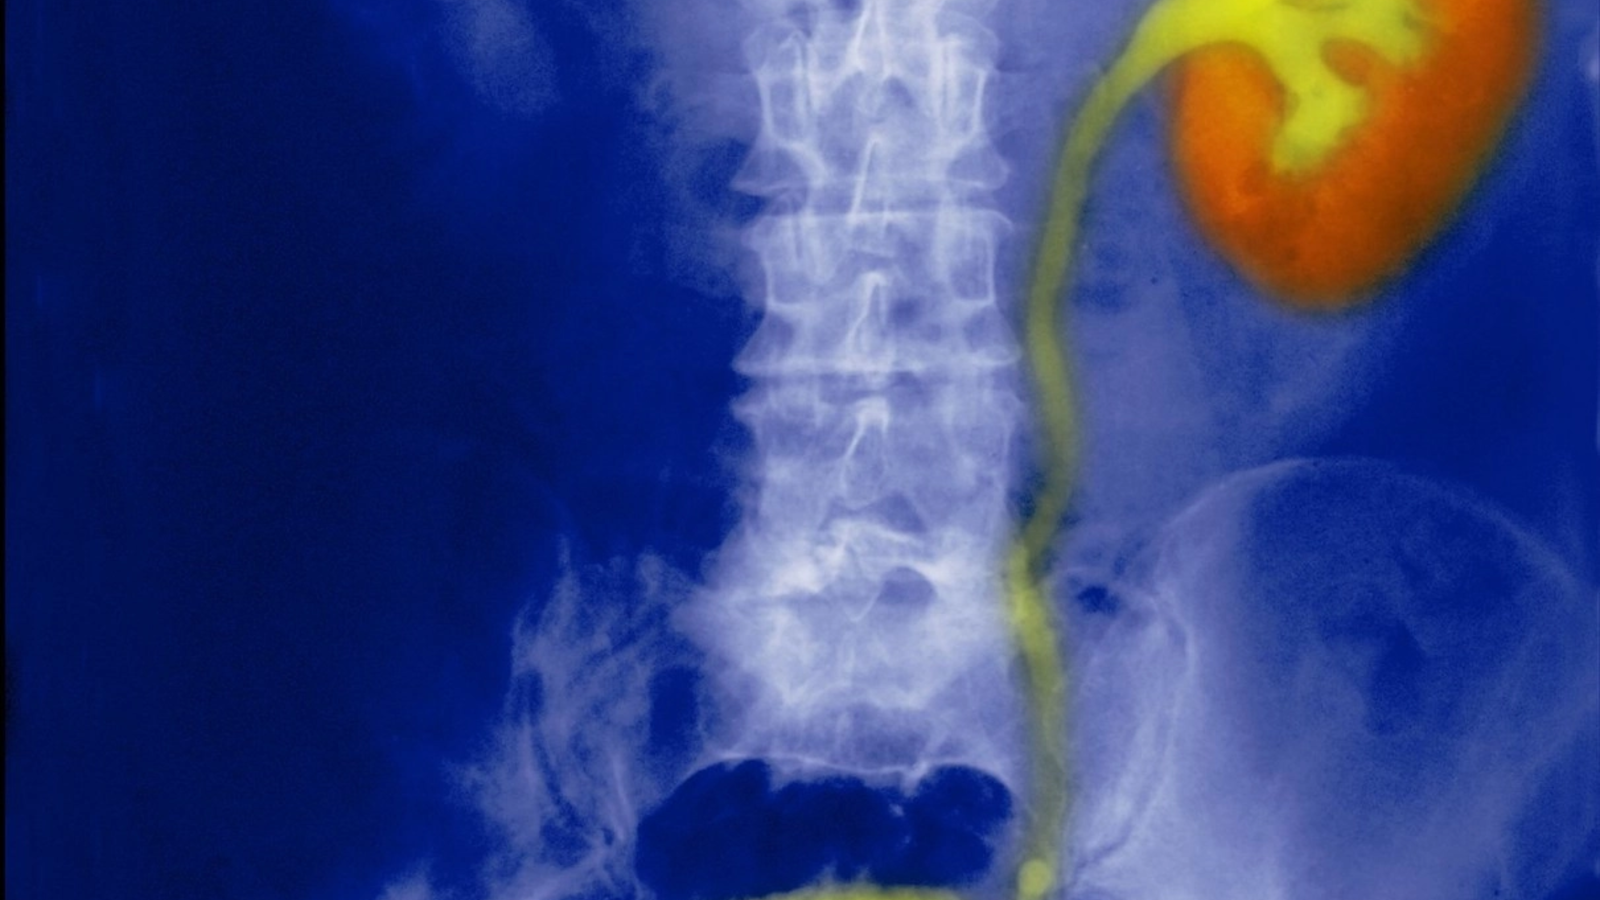

O echipă de cercetători de la Institutul European de Oncologie și Universitatea din Milano a făcut o descoperire importantă care ar putea schimba modul în care sunt diagnosticate și tratate formele agresive de cancer la vezica urinară.

Studiul, publicat în revista Nature Communications, a identificat o proteină numită Numb care joacă un rol crucial în dezvoltarea tumorilor. Această proteină, care există în mod normal în țesutul vezicii urinare, lipsește la peste 40% dintre pacienții cu cancer vezical, scrie La Repubblica.

Profesorul Salvatore Pece, directorul adjunct al Departamentului de oncologie din cadrul Universității din Milano, afirmă că atunci când proteina Numb dispare, se declanșează o serie de reacții care fac tumoarea să se răspândească rapid și să devină invazivă, pătrunzând din straturile superficiale ale vezicii în cele profunde.